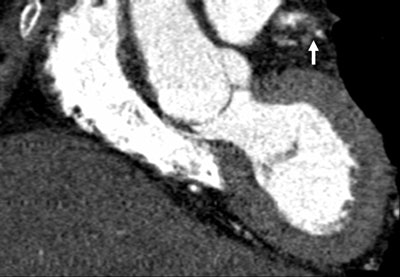

| Images 1-7 shown top to bottom: A 59-year-old man presented with atypical chest pain. A circumscribed, short-segment high-degree stenosis (arrow) in the proximal LAD is difficult to detect on transverse (1), sagittal (2), or coronal (3) multiplanar reformats. Use of advanced visualization tools with automated extraction of the coronary artery tree (4) and automated display as curved multiplanar reformat (5) clearly identifies the lesion, also seen in the 3D view (6) and confirmed on conventional catheter angiography (7). All images courtesy of Dr. U. Joseph Schoepf. |